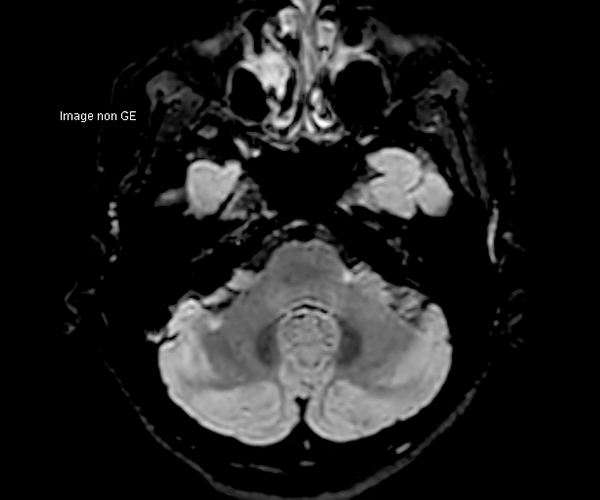

Concernant l’imagerie cérébrale, l’IRM 3T permet d’augmenter la sensibilité de détection de lésions ischémiques aiguës de petite taille, notamment chez les patients adressés pour accident ischémique transitoire (accident vasculaire cérébral), grâce à la séquence de diffusion dont le signal et la résolution sont augmentés.

La séquence de perfusion par marquage des spins artériels (ASL) étudiant la perfusion cérébrale sans injection trouve pleinement son application à 3T dans la pathologie vasculaire, la caractérisation et le suivi post-thérapeutique des lésions tumorales, les démences et certaines pathologies psychiatriques.